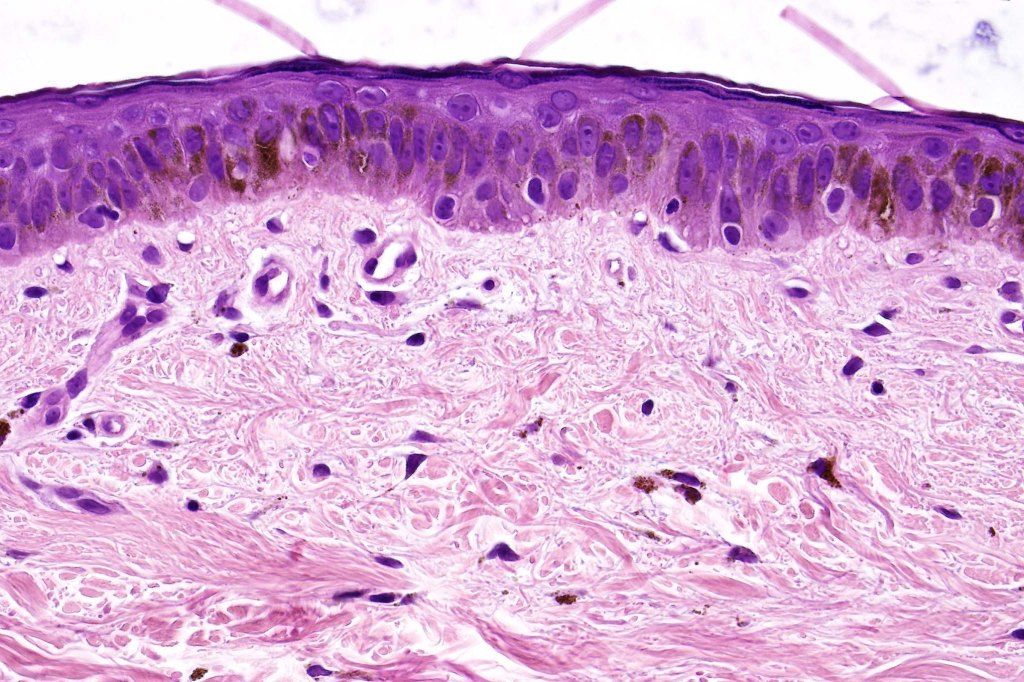

Histological features

•The epidermis is of normal thickness or less often acanthotic and lacks the lentiginous hyperplasia seen in actinic lentigo

•Hyperkeratosis but no parakeratosis

•Often pigmented but may be achromic

•Keratinocytes are enlarged & contain uniform, often vertically orientated, oval nuclei up to twice the size of uninvolved ones

•Absence of cytological atypia or mitoses above the basal layer

•Melanocytes may be present in increased numbers